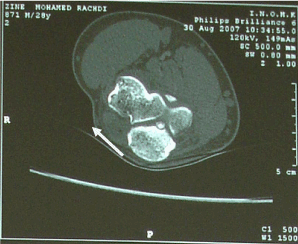

Mr Z, 30 years old , right handed consulted for an 18 months history of spontaneously occuring pain in his right elbow. It was inflammatory type, permanent and resistant to analgesic drugs (paracetamol). The pain was located at the outer side of the elbow and was radiating to the dorsal side of the forearm. He has had multiple epicondyle injections without efficiency in pain relief . Clinical examination revealed a sharp pain caused by lateral epicondyle palpation, painful mobility of the elbow with a flessum of 20 °, whereas pronosupination was normal . X-rays investigation was normal (Fig 1 and 2), biology and electromyogram (EMG) were abnormal. Ultrasonography of the right elbow showed significant synovial thickening with color doppler hyperhemia associated with intra-articular effusion. Scintigraphy showed diffuse hyperfixation of the elbow. MRI showed significant bone and of soft tissue oedema associated with joint effusion. The CT revealed a calcified nidus of the large sigmoid cavity of the ulna surrounded by a clear border within a poorly limited osteocondensation with intra-articular effusion (Fig. 3). The diagnosis of intra-articular osteoid osteoma of the elbow was confirmed and the aspirin test was positive. Because of the difficulty of the surgical approach, percutaneous resection was used under CT guidance. Loco-regional anaesthesia (axillary block) following the classic aseptic rules was done. A guide pin was placed posterolaterally after CT scan and then using a motorized 8mm diameter trephine, a block resection of the osteoid osteoma was performed. The CT control confirmed the complete resection of the nidus (Fig.4). A postoperative immobilization of seven days has been prescribed. The evolution was marked by a complete and immediate disappearance of the pain and a recovery of the elbow mobility. Histological examination confirmed the diagnosis of osteoid osteoma. Thirteen months after surgery, the elbow was painless, with complete mobility, and radiological control showed the ossification of the resected bone core.

Fig 3: calcified nidus of the large sigmoid cavity of the ulna surrounded by a clear border